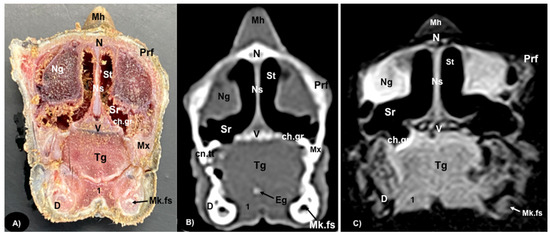

3.1. Anatomical Sections

3.2. Computed Tomography (CT)

3.3. Magnetic Resonance Imaging (MRI)